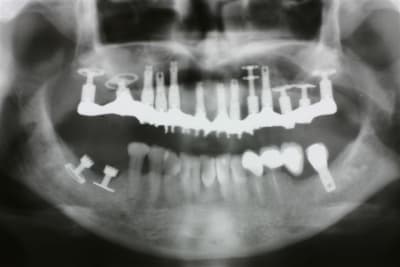

Le cas 2 c est pour plus tard car un peu plus long à expliquer mais là ça commençait par un échec de greffe avec de l iliaque pour remplacer 47 46...

La praticien de la patiente pose ds une greffe molle 3 cylindres et en garde un seul , le mésial et comme par hasard celui qui ds son os natif et pas ds le greffon

Je lui ai posé une première fois une plaque sans ostéotension car cela n existait pas à l époque... Mierda la plaque s expose en lingual et je dois me résoudre à la dépose :-(

Je laisse le site au repos et je viens qques moins plus y reposer un monodisk 8G2DM7 avec apport de nanobone et prfs... Encore mierda il se mobilise et se fibrose

Entre temps je lui fais 3 séances d ostéotension manuelle qui rend le site un plus vascularisé et donc pus exploitable... Je me décide à déposer ce disk en vue simplement de refermer le site sur un nouvel apport de nanobone et là lors de la dépose le site m inspire : bien sanglant et très belle os corticalisé sous le disk : je me jette ds la bagarre et je repose de suite un 9G2DM que je peux bien bolquer avec une vis d ostéosynthèse en vestibulaire ds cette belle corticale sous le disk. Nanobone + PRF + Membrane de Jason...et laissé en enfoui qques mois

Au bout de ces qques mois prise d empreinte sur un disk sonore comme un cylindre et totalement fixe sans l ombre d une sensibilité

Evidemment cette patiente m a tjs posé bcp de question mais je lui avais posé au maxillaire une plaque et un disk qui s étaient intégrés sans aucun ennui donc elle savait que seule de mauvaises circonstances nous avaient empêché de réussir ds le secteur 40

Entre la greffe et mon dernier disk 7 ans sont passés mais je pense que c est effectivement le fait d intervenir plusieurs fois en dépériostant et donc en dévascularisant le site qui nous fait aller ds le mur... En fait j ai laissé de long tps morts pour que l os récupère et j ai choisi de réimplanter de suite lors de la dernière dépose pour éviter encore une meurtrissure supplémentaire pour ce site par un n-ième passage chirurgical à cet endroit

C est pas tellement praticien dépendant mais ça nécesite de raisonner plus que pour la pose de simpe cylindres ds des kms d os alvéolaire

Premier précepte de l implanto basale : tjs duu fixe

Deuxième précepte de l implanto basqle : tjs des ancrages postérieurs donc on va loin au bout des max et mand même si tu peux trouver ça inutile ds un premier tps

Troisième précepte de l implanto basale : qd les volumes sont réduits comme ici où tout le secteur distal est en mono disk ou pire même en plaque, on augmente le nombre d implants au max pour répartir les forces... Il ne faut jamais perdre de vue que même si c est très solide une fois intégré, on passe par la MCI où la solidité est précaire au début...